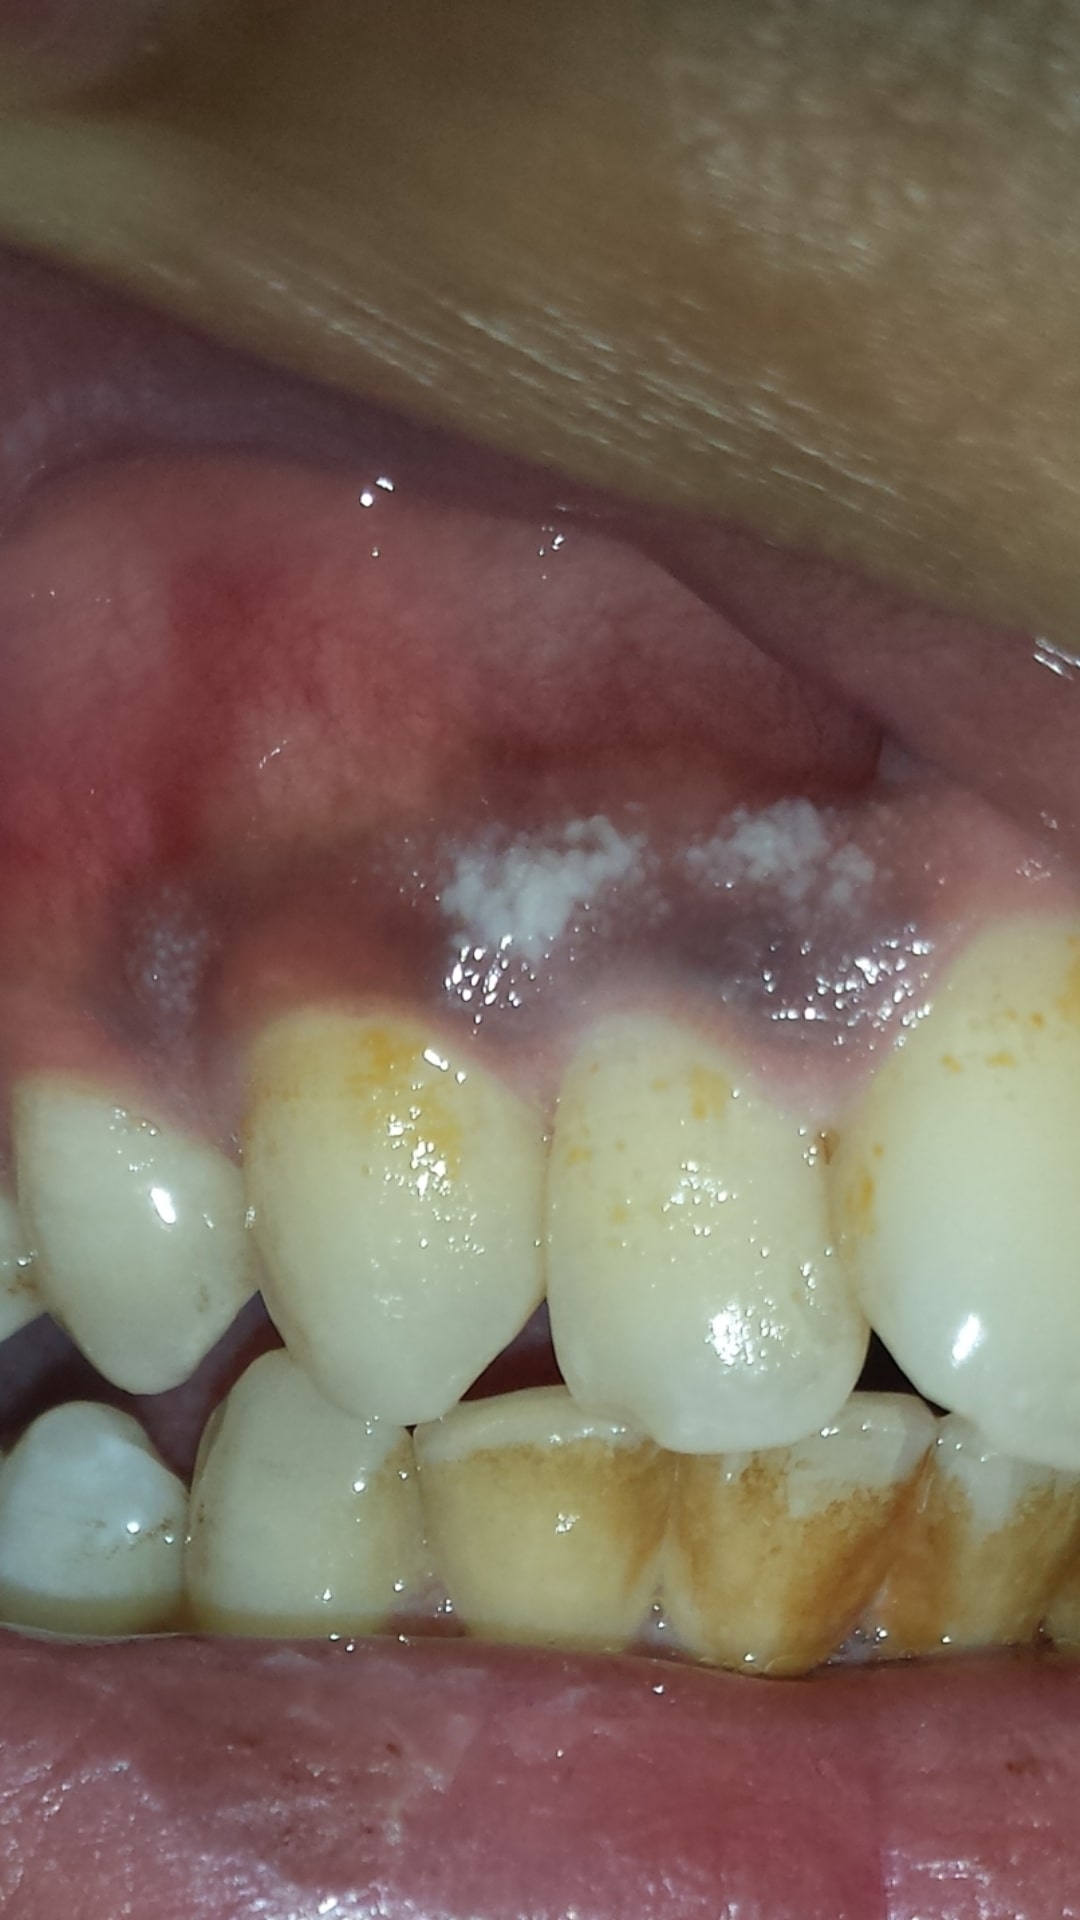

White dots on gums can be caused by a variety of factors, including canker sores, oral thrush, or even oral cancer. Canker sores are small, painful ulcers that can develop on the gums and other areas of the mouth. Oral thrush is a fungal infection that can also cause white patches on the gums. In more severe cases, white dots on gums can be a symptom of oral cancer, which requires immediate medical attention.

Additionally, poor oral hygiene, smoking, or certain medications can also contribute to the development of white dots on the gums. It is important to consult with a dentist or healthcare provider to determine the underlying cause of the white spots and to determine the appropriate treatment plan.